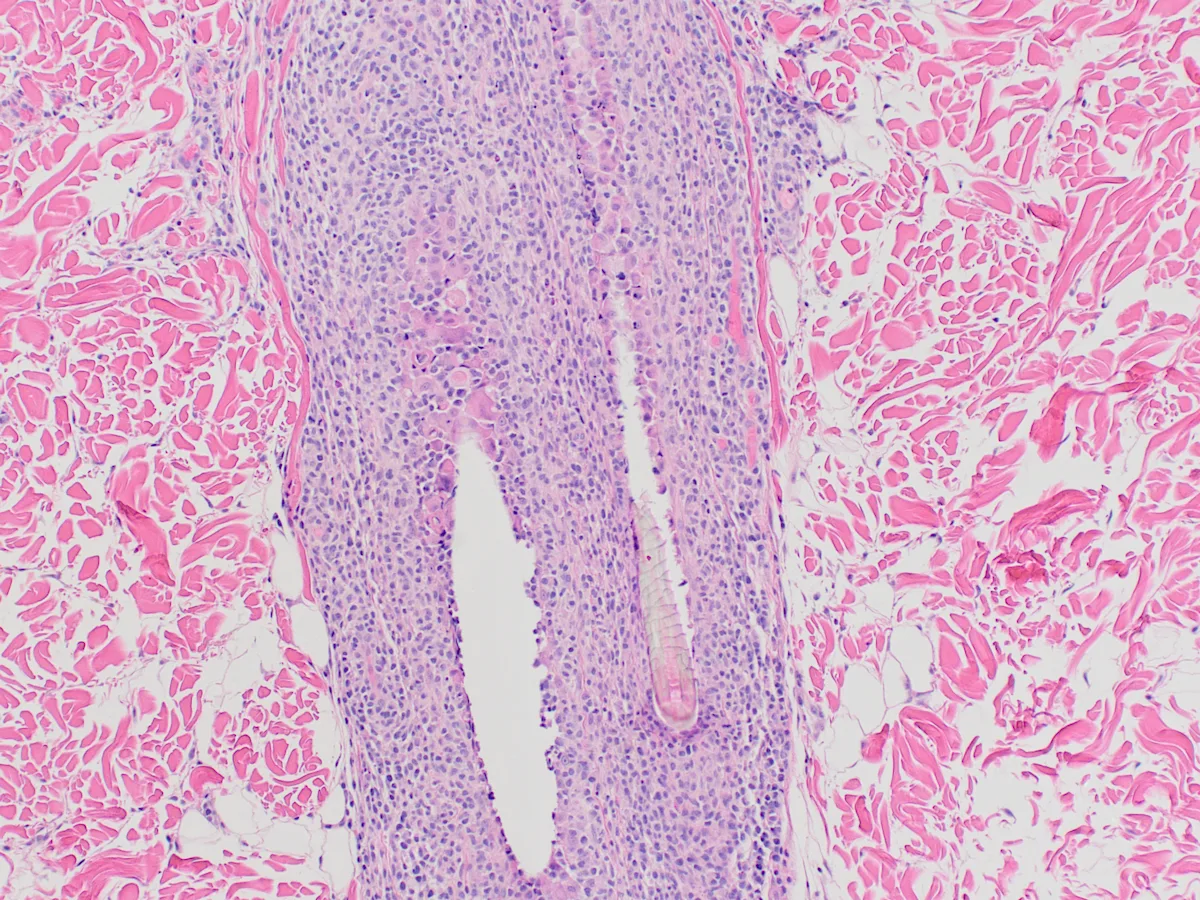

Inflammation is characterized by infiltration of neoplastic T lymphocytes with a tropism for the epidermal or mucosal epithelium, as well as adnexal structures, especially the follicular wall (Figure 4).7,12 Pautrier’s microabscesses (intraepithelial neoplastic lymphocytes diffusely in the epidermis or in aggregates) may be noted.7 Neoplastic lymphocytes that infiltrate apocrine sweat glands occur in 70% of cases and are considered diagnostic (Figure 5).6,7

Neoplastic lymphocytes infiltrating the follicular wall. Image courtesy of Dr. Shannon Martinson